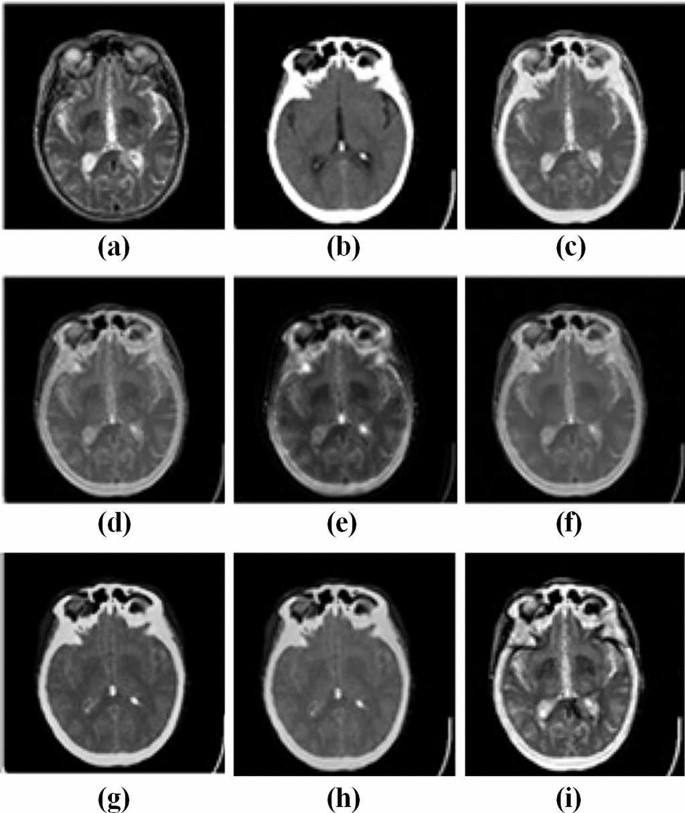

Figures 3 and 4 represent the source images and their respective multi-modality fused biomedical images obtained from the LEPN (Zhu et al. 2019), DSA (Zhu et al. 2020), CNN (Kumar et al. 2020), EGDM (Lu et al. 2014), DDcGAN (Ma et al. 2020), 3GANs (Wang et al. 2019) and the proposed approach. It is clearly shown that the obtained results have better modality as compared to the competitive approaches. Although, the existing approaches such as LEPN (Zhu et al. 2019), DSA (Zhu et al. 2020), CNN (Kumar et al. 2020), EGDM (Lu et al. 2014), DDcGAN (Ma et al. 2020), and 3GANs (Wang et al. 2019) provide significant visual results but have little edge and texture distortion. Figures 3i and 4j show the obtained results from the proposed approach. These images prove that the proposed approach provides a better visual appearance of the obtained multi-modality fused images.

Analysis of multi-modality biomedical fusion approaches: a MRI, b CT, c LEPN (Zhu et al. 2019), d DSA (Zhu et al. 2020), e CNN (Kumar et al. 2020), f EGDM (Lu et al. 2014), g DDcGAN (Ma et al. 2020), and h 3GANs (Wang et al. 2019) and i proposed approach